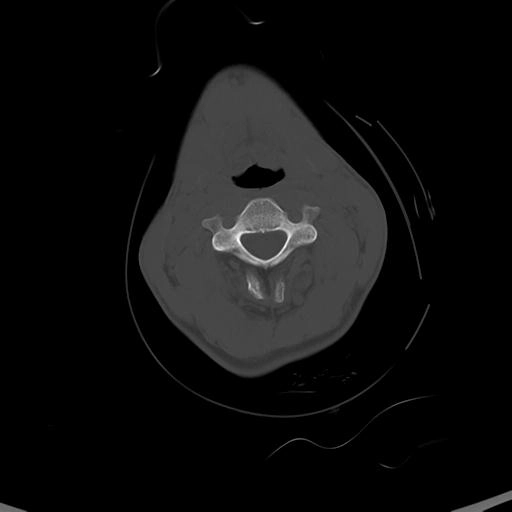

• Gãy xương phức tạp

Gãy xương Le Fort (Le Fort fracture classification)